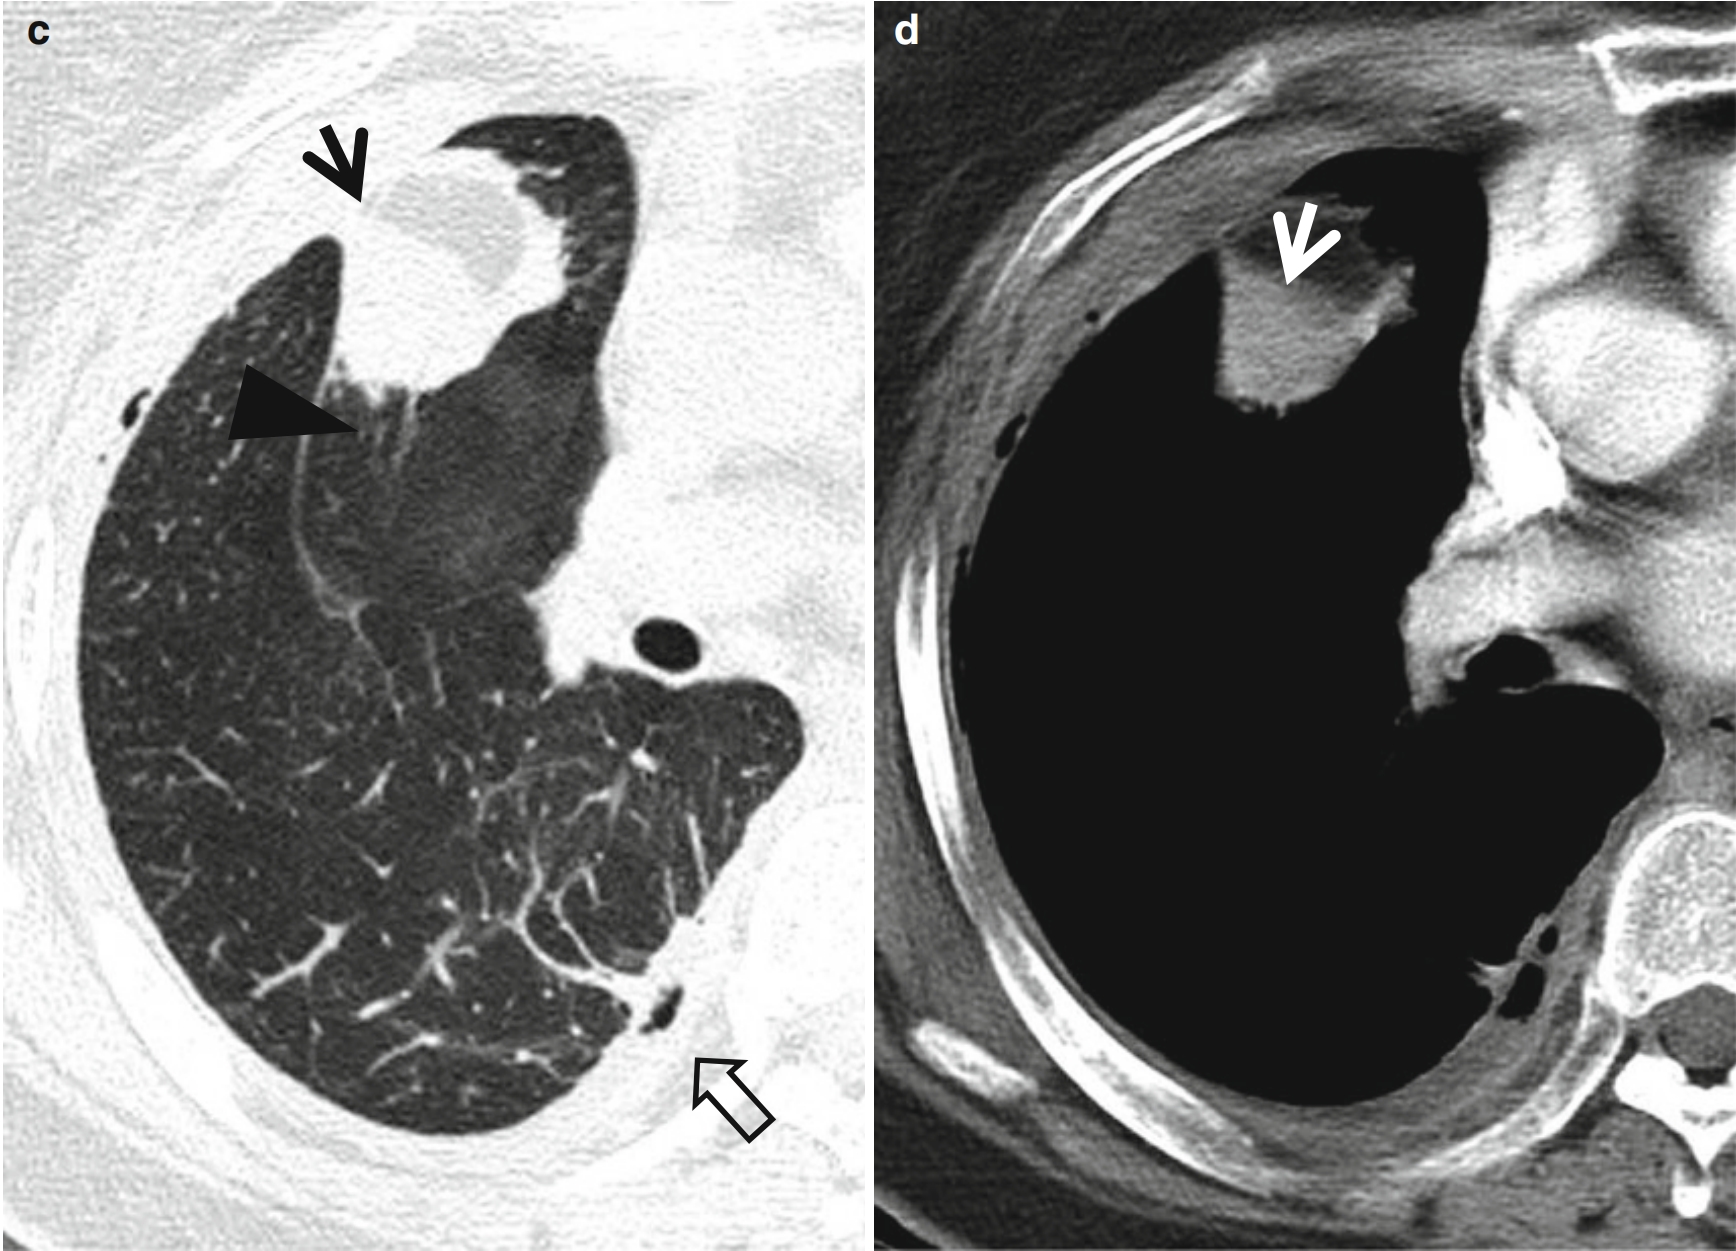

0b64c39f16092c9a61035059ec913ca0.png4f37eedeb011e9dec1219e03c89ea903.png图2 肿块样圆形肺不张。

男,63岁,主诉轻微呼吸困难和咳嗽。

(b,c)薄层CT(层厚=1.5mm)显示:分别在右上叶支气管分叉水平(b)和右肺中间段支气管水平(e),可见与前胸膜粘连的右肺上叶圆形肺不张(箭头所示);并可见血管性的条索状软组织密度影(楔形箭头所示),从圆形肺不张的后缘延伸至肺门。另可见右后部胸腔积液和胸膜增厚(空心箭头所示)。

(d)与c图相同位置软组织窗显示右肺上叶圆形肺不张(箭头所示),同时可见右侧胸腔积液和胸膜增厚。